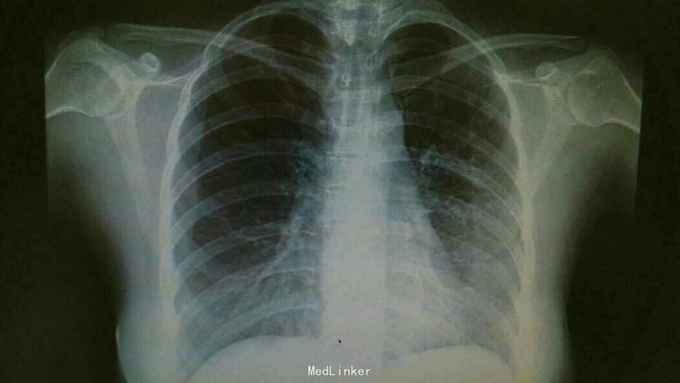

诊断:肺炎支原体费炎。 治疗:入院予以抗感染,止咳化痰等治疗。治疗后复查胸片,左中下肺炎症好转。

随访:嘱患者1周后门诊复查。 讨论:支原体肺炎为常看不典型肺炎,治疗上主要抗感染治疗,一般疗程为3周。临床上主要与肺结核相鉴别。